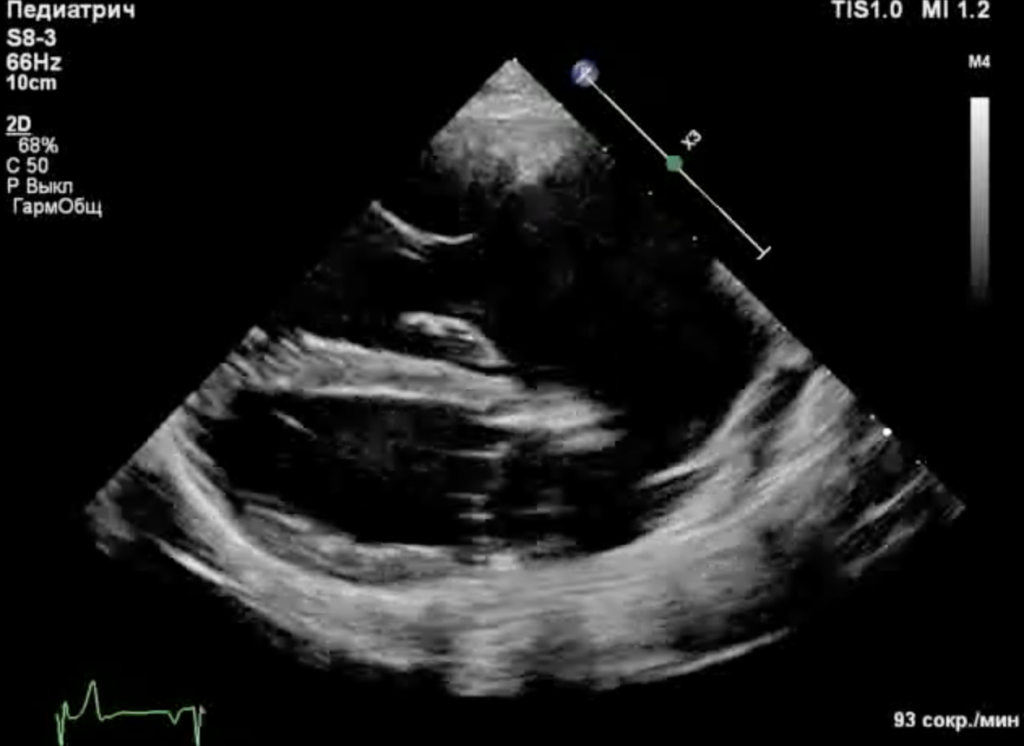

Собака находилась под наблюдением с 5-месячного возраста. При эхокардиографическом исследовании были выявлены следующие аномалии (фото 1-3):

- Выраженная дилатация правого предсердия (47 мм) и правого желудочка (конечный диастолический размер – 34 мм).

- Неделаминированная и малоподвижная септальная створка.

- Укороченные хорды.

- Выраженная регургитация (massive).

- Гепатомегалия, обусловленная застоем крови в системных венах.